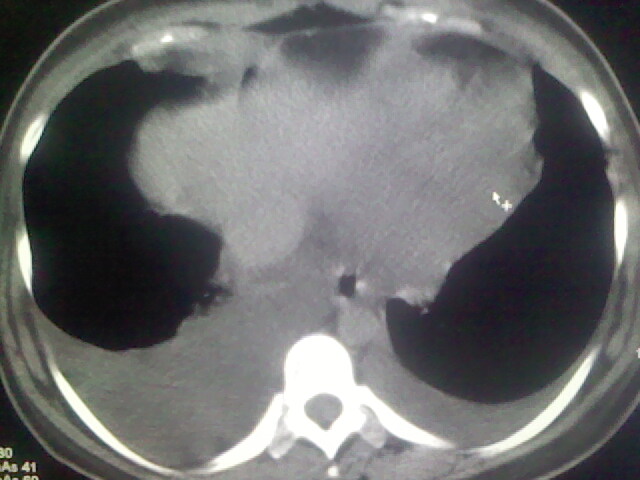

女,24,剖腹产后,突觉胸痛,干咳,不能平卧

双肺“肺泡性肺水肿” “胸腔积液”!

全心衰导致积液、肺水肿。不知手术前有无心脏病变?

临床资料及影象表现支持围产期扩张型心肌病改变,心衰。

考虑产后心肌病,心功能不全,肺水肿,双侧胸腔积液。不排除羊水栓塞可能。